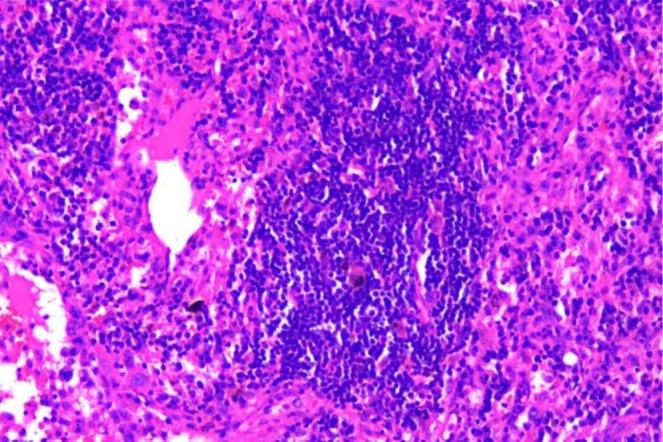

Rosai-Dorfman disease (RDD), a rare form of histiocytosis, predominantly affects young individuals. Clinically categorized into nodal and extranodal subtypes, the disease primarily involves systemic lymph nodes with possible involvement of other organs. This variability in organ involvement leads to diverse clinical manifestations and nonspecific imaging findings, contributing to frequent diagnostic challenges and misdiagnosis. Histopathologically, the characteristic cells demonstrate S100+, CD68+, and CD1a-negative immunophenotype. We present a rare geriatric case of RDD, which may enhance diagnostic awareness and clinical management of this condition. Further research is warranted to advance our understanding of RDD pathogenesis and therapeutic strategies.